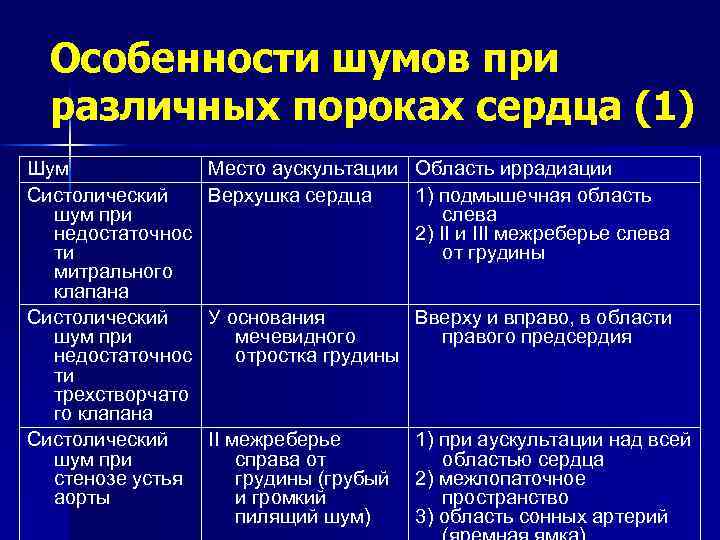

Особенности шумов при различных пороках сердца (1) Шум Систолический шум при недостаточнос ти митрального клапана Систолический шум при недостаточнос ти трехстворчато го клапана Систолический шум при стенозе устья аорты Место аускультации Область иррадиации Верхушка сердца 1) подмышечная область слева 2) II и III межреберье слева от грудины У основания Вверху и вправо, в области мечевидного правого предсердия отростка грудины II межреберье справа от грудины (грубый и громкий пилящий шум) 1) при аускультации над всей областью сердца 2) межлопаточное пространство 3) область сонных артерий